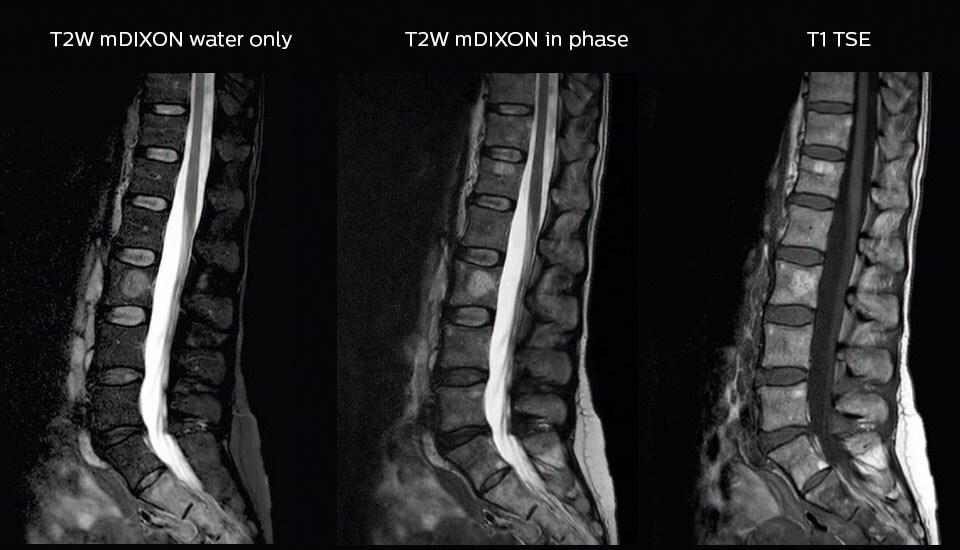

“In our lumbar spine MRI, the value of mDIXON TSE is so obvious. Normally we perform T1 and T2 scans in sagittal and transverse orientation.It used to take too much time to add a sagittal T2 with good fat suppression.But now, using mDIXON TSE, we get the sagittal T2 fat suppressed images ‘for free’, that is: without adding time.” “Diagnostically that is a great benefit. I sometimes see abnormalities in the fat suppressed sagittal T2 that would be quite challenging to notice in the T2 without fat suppression. There have been several diagnoses that I could make easier because of our exam setup with mDIXON TSE, such as sacrum insufficiency fractures and sacroileitis; these were more challenging with our previous exam setup.”